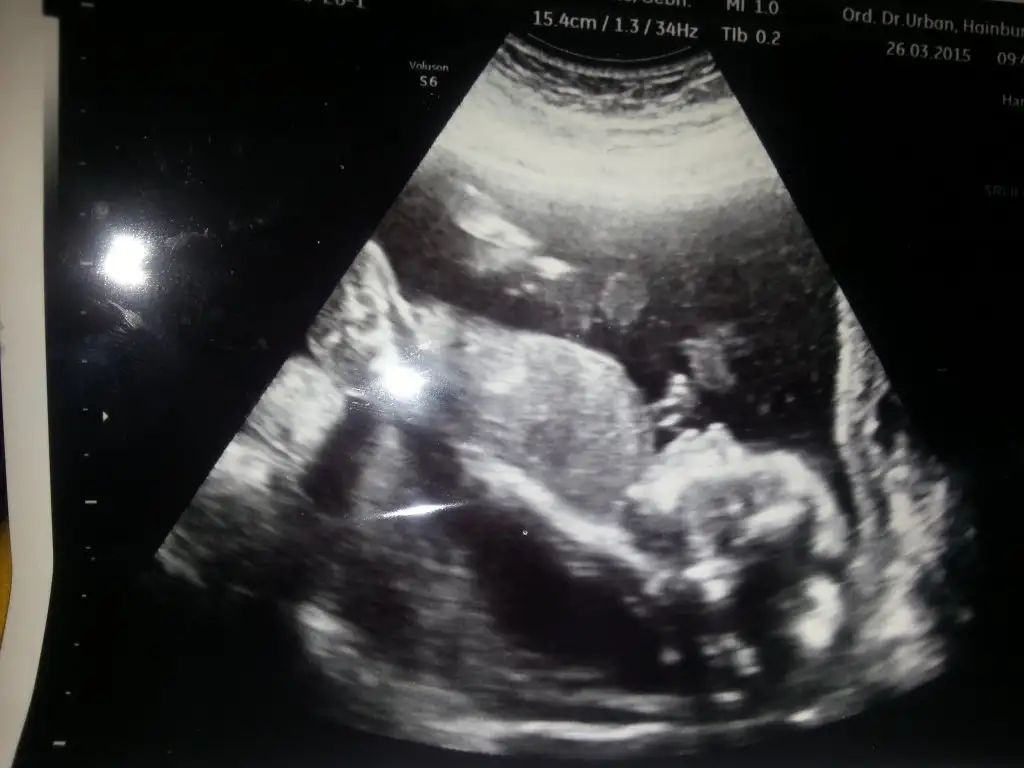

Kız gibi geldi ama sanki yüzü de erkek gibi geldi :) Bilemediimm.. Sağlıkla gelsincanlar bizede tahmin yapın 12 haftalık oldul

Sanki cikinti var erkek gibi .....kızlar bana da yorum yapın 12+2 yiz sizce cinsiyeti ne olabilir ?

çıkıntı var evet ama kızlarda da çıkıntı oluyor sanırım nuba göre çıkıntı paralelse kız daha dikse erkek oluyormuş anladığım kadarıyla burda da paralel gibi duruyor ama bilmiyorumSanki cikinti var erkek gibi .....

Ben de paralel sanki diye kız dicektim ama, belli bir haftadan sonra kızda çıkıntı azalıyor sanırım. Erkek öyle kalıyorçıkıntı var evet ama kızlarda da çıkıntı oluyor sanırım nuba göre çıkıntı paralelse kız daha dikse erkek oluyormuş anladığım kadarıyla burda da paralel gibi duruyor ama bilmiyorum

Sevalvim anladimda deilde tahmin ediyoz :) bebisin belinden poposuna kadar bi cizik ciziyoz yataysa k8z dikeyse erkek bide bebis kizami erkegemi daha cok benziyo cikinti varmi ona bakiyoz. :)) yanildimuzda oluyo canim bende ilk bebis arastira arastira bu halegeldik :)) bebis 20 haftalik hala kendi bebisim ney bilmiyorum.. yeni arkadaslar bide siz bakin benom bebise icinizden ne geciyi ...Ya nasıl anliyon merveeee